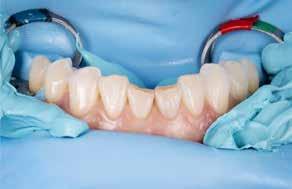

Der planlægges alignerbehandling af begge kæber med intrusion af 1+1 og 2,1-1,2, nivellering af trangstilling UK med interproksimal reduktion (IPR) (Fig. 2 A, B) og senere IPR OK for reduktion af dark triangles mellem incisiverne efter nivellering. Patienten instrueres i at benytte alignere 20-22 timer/ dag med alignerskift hver 7. dag, og patienten ses hver 3.-8. uge under forløbet. Den første alignerserie består af 16 alignere for nivellering OK/UK og IPR i UK (Fig. 2). Efter denne serie planlægges IPR mellem incisiverne i OK for reduktion af dark triangles (Fig. 3) samt yderligere intrusion af OK og UK-fronten i 12 refinement-alignere. Patienten udviser god kooperation og er meget tilfreds med alignerapparaturet, som er mindre synligt end det faste apparatur (Fig. 4).

Behandlingen afsluttes med yderligere refinement-alignere for finindstilling af okklusionen, og efter 11 måneders ortodontisk behandling er der opnået normale relationer i alle tre